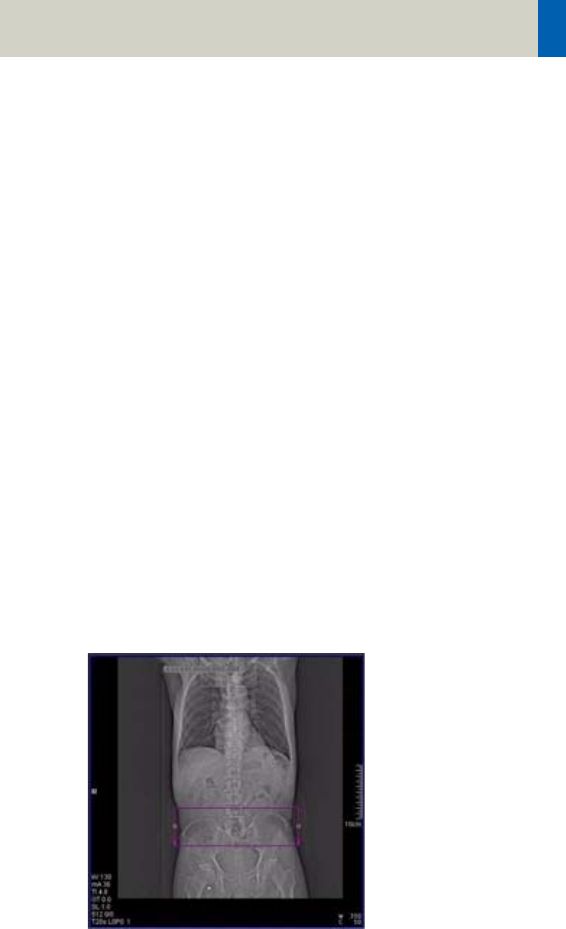

Principle of automatic tube current adaptation by

CARE Dose 4D for a spiral scan from shoulder to pelvis

(very high table feed for demonstration): High tube

current and strong modulation in shoulder and pelvis,

lower tube current and low modulation in abdomen

and thorax. The dotted lines represent the min. and

max. tube current at the corresponding table position

and result from the attenuation profile of the Topo-

gram.

The mAs value displayed in the user interface and in

the patient protocol is the mean (eff.) mAs value for

the scan range.

The mAs value recorded in the images is the local (eff.)

mAs value.